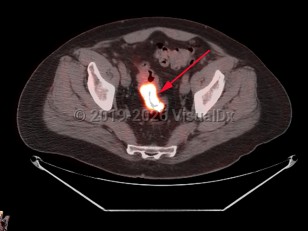

Rectal carcinomaRectal carcinoma

Metastatic pancreatic carcinomaMetastatic pancreatic carcinoma